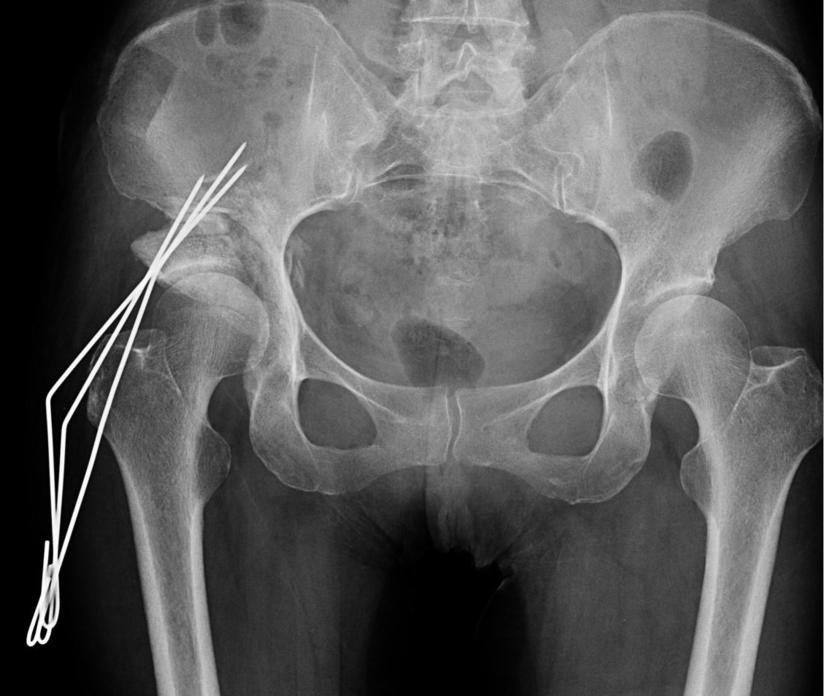

向股骨头坏死宣战 我院骨一科成功开展我市首例股骨头坏死髓心减压 打压植骨 腓骨支撑手术 治疗